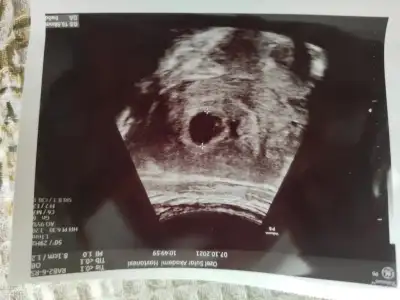

Progestan verdiler ancak kalp atımı duyulmadı. Sanırım kaybettim bebeğimi ama ultrasonda Bi hareket vardı kalp atımı şeklinde. 1 hafta daha bekleyelim ama sağlıklı bi gebelik ilerlemesi göremiyorum dedi doktor. Kaç kere ipten döndü bu gebelik daha da dönmez snırım kabullenmem gerek...

Selam kızlar geldim hastaneden, maalesef biraz hayal kırıklığı var kalp atışı dinletmedi. Kese ve bebek var kalp atışı için 15 gün sonra gel dedi, hocam bu haftalarda duyulması gerekmez mi dedim yok henüz duyulmaz dedi. Ama arkadaşlar duymuş dedim, herkesin döllenme zamanı farklıdır dedi, ama ben ovulasyon takibi yaptım hocam dedim, artık ters ters bakmaya başlayınca sustum 😂 kadın herşey gayet normal dedi pozitif konuştu ama benim moralim bozuk tabi, o kadar bekledim 😭 kontrol süresi 10 günmüş hastanede, 15 gün sonra tekrar gidip tekrar muayene ücreti ödeyecem bir de 🤣 neyse en azından dış gebelik falan değil ama işte ne yapalım ☺️